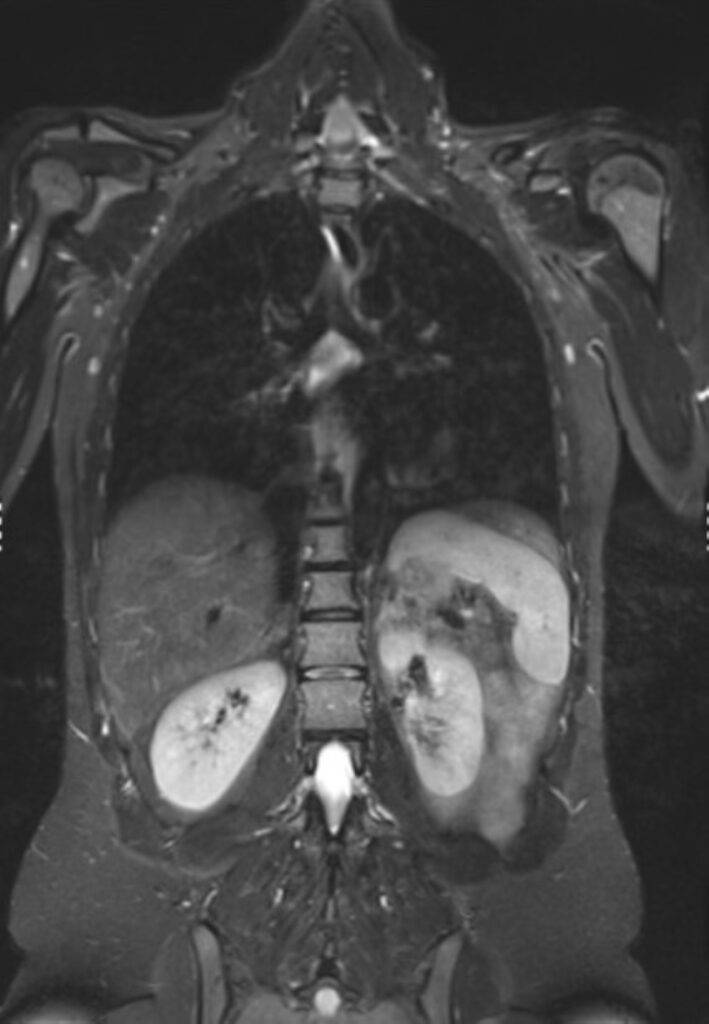

Eine Ganzkörper MRT liefert hochauflösende Bilder des gesamten Körpers von Kopf bis Fuß und ist daher ideal für Vorsorgeuntersuchungen oder zur Verlaufsbeurteilung von malignen Erkrankungen:

- Die Ganzkörper MRT kann auch der Früherkennung von malignen Tumorerkrankungen, beispielsweise von Bronchial- oder Nierenzellkarzinomen, im Sinne eines Screenings asymptomatischer Patienten dienen.

- Wurde bereits eine Tumorerkrankung diagnostiziert, kann die Ganzkörper MRT nützlich sein, die momentane Ausbreitung präzise zu beurteilen. Auch Fernmetastasen können durch eine Ganzkörperuntersuchung frühzeitig festgestellt werden. Die MRT ist aufgrund des höheren Weichteilkontrasts speziell in den Organen des Oberbauchs, der Lymphknoten, des Gehirns und des gesamten Skelettsystems hochpräzise bei der Erkennung von Metastasen.

Die Ganzkörper-MRT stellt eine besonders detaillierte Methode in der medizinischen Bildgebung dar, die es ermöglicht, ohne die Verwendung ionisierender Strahlung, das Innenleben unseres Körpers umfassend zu visualisieren. Mittels starker Magnetfelder und Radiowellen wird der Körper in Gänze erfasst, wodurch ein vollständiges Bild der verschiedenen Organsysteme, der Gefäße sowie der Weichteile des Bewegungsapparates wie Muskeln, Sehnen und Gelenke ermöglicht wird.

Dank der herausragenden Weichteildarstellung und der Möglichkeit, hochauflösende, detailreiche Bilder zu erzeugen, bietet die Ganzkörper MRT eine unvergleichliche Diagnostik.